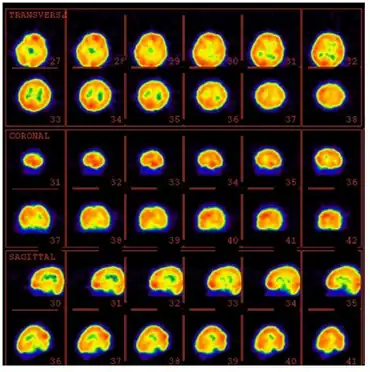

The most effective way of confirming LKS is by obtaining overnight sleep EEGs, including EEGs in all stages of sleep. Many conditions like demyelination and brain tumors can be ruled out by using magnetic resonance imaging (MRI). In LKS, fluorodeoxyglucose (FDG) and positron emission tomography (PET) scanning can show decreased metabolism in one or both temporal lobes - hypermetabolism has been seen in patients with acquired epileptic aphasia.[5]